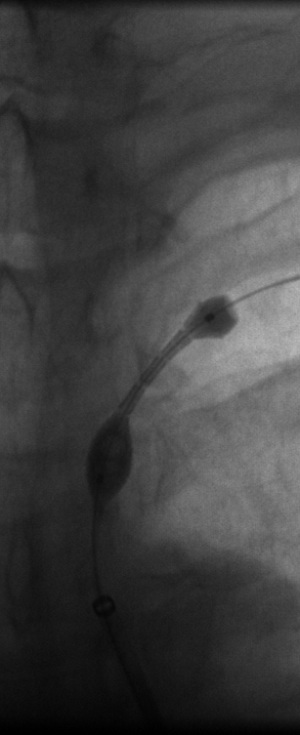

The 4 images you see above were recorded by me during primary stenting of irregular atherosclerotic stenosis of the left subclavian artery in a 54-year-old hispanic female who was referred to my interventional radiology clinic for management of the stenosis. She had presented to her primary care physician with symptoms of hindbrain ischemia upon using her left upper limb and earlier workup confirmed left subclavian arterial stenosis. The 2 top images illustrate the character and severity of her disease, the first image in the bottom row shows the process of balloon-expandable stenting of the disease, while the 2nd image in the bottom row reveals complete elimination of the stenosis and reappearance of the left vertebral and internal mammary arteires, which were invisible on the pre-intervention angiograms reflecting the severity of the stenosis.